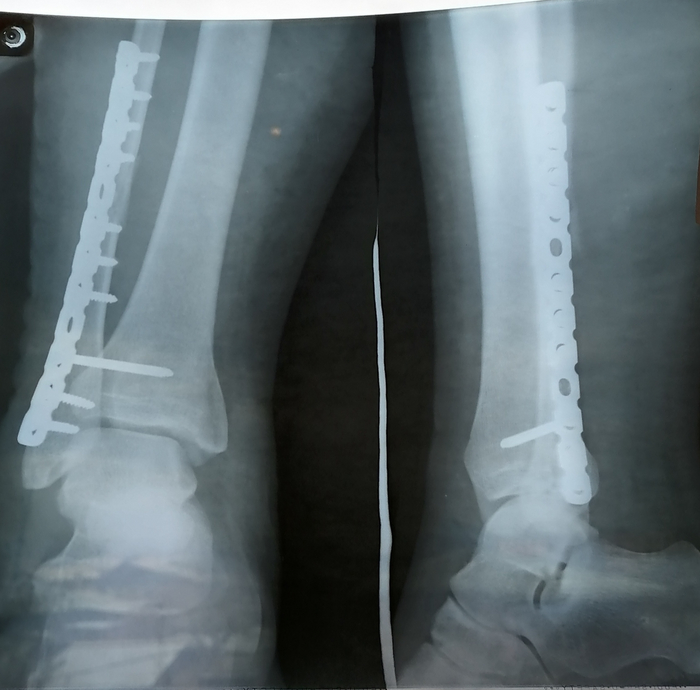

Кололи обезболивающее, пока я не отказалась сама. Я наконец-то могла спать хотя бы на боку, а когда мне привезли костыли - даже сама ходить в туалет (пока я не лишилась этой привилегии, я ее даже не ценила), хотя врач вставать не разрешал, и когда он меня застукал - отругал, но запрещать уже не стал, только объяснил, что титановую конструкцию в ноге нужно будет через пару лет снять, так как она будет мне мешать.

Еще не Росомаха, но уже частично Железная леди